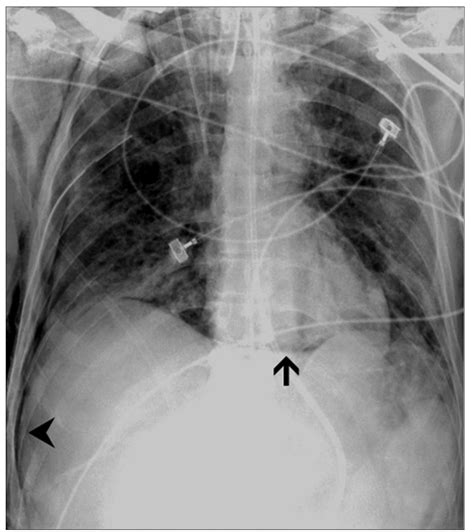

The Deep Sulcus Sign is characterized by an abnormally deep and lucent (dark) costophrenic angle on a supine chest X-ray. Under normal circumstances, the costophrenic angle—the sharp point where the diaphragm meets the ribs—should be relatively shallow. When a pneumothorax occurs in a supine patient, the free air tracks to the most non-dependent part of the pleural space, which, in this position, is the anterior and lateral costophrenic sulcus.

This accumulation of air causes the costophrenic angle to appear hyperlucent and deeper than usual, often extending further inferiorly than the contralateral side. Recognizing this sign is paramount because, in supine radiography, standard signs of pneumothorax—such as the visualization of a visceral pleural line—are frequently absent or obscured, leading to a high rate of missed diagnoses.

A missed pneumothorax can rapidly progress into a tension pneumothorax, a life-threatening medical emergency. Tension pneumothorax occurs when the trapped air creates increasing pressure, causing the mediastinum to shift, compressing the heart and major blood vessels, and leading to obstructive shock. By detecting the Deep Sulcus Sign early, medical teams can intervene with needle decompression or chest tube placement before the patient’s hemodynamic stability deteriorates.